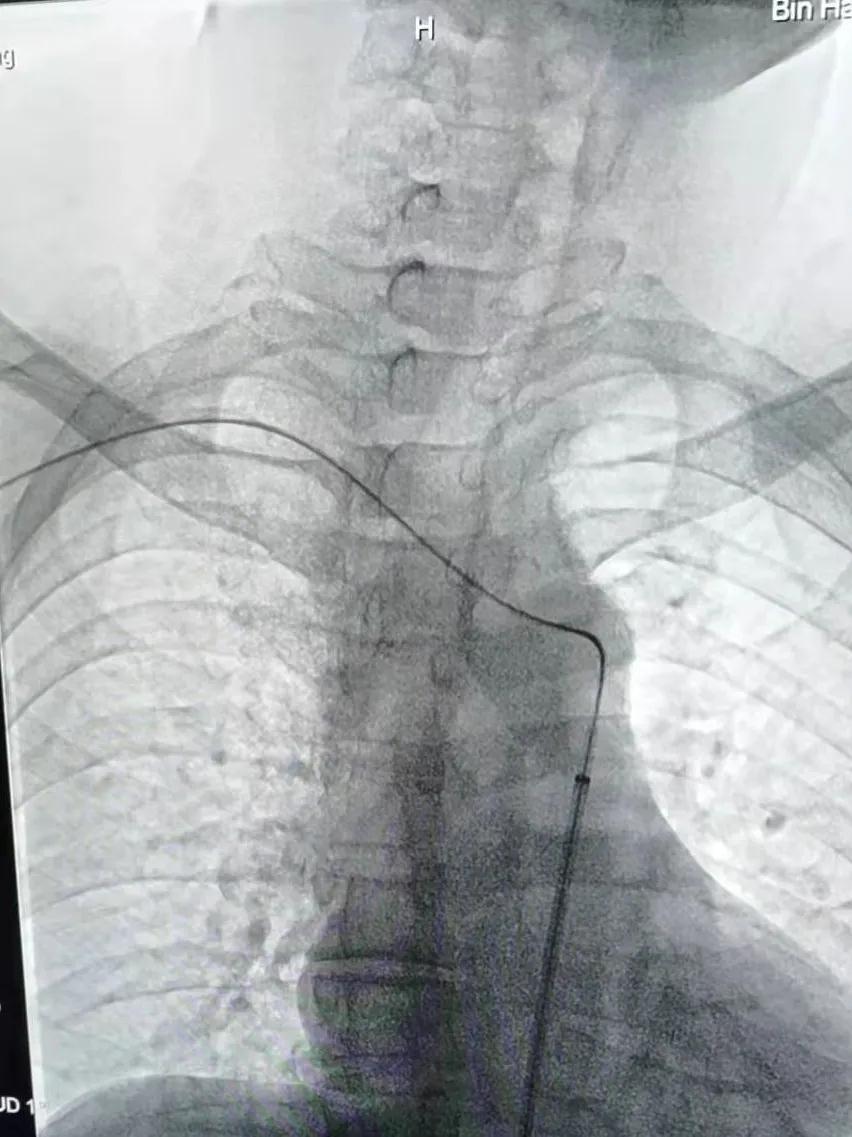

在征得王先生及家人同意后,魏主任組織介入團隊進行術前討論,依據患者病情擬定了詳細的手術方案,手術由魏主任親自操作,在手術中意想不到的遇到了重重困難:一是斑塊硬開通困難,二是斑塊脫落形成栓塞,三是病灶在夾層,四是支架不能堵塞椎動脈等,給手術帶來很大風險,憑借多年的臨床實踐,終于把血管開通、支架植入。后經造影顯示:右鎖骨下動脈支架置入后恢復前向血流,不再盜血,手術歷時4個小時,整個過程可謂“驚心動魄”。

建立右側肱動脈與右側股動脈軌道